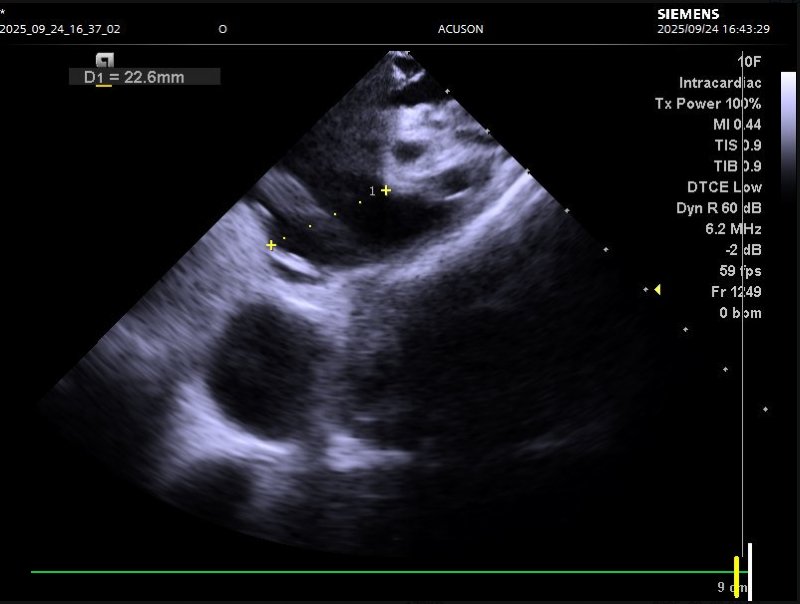

针对这一复杂病情,心血管内科系主任姜大明带领心律失常介入团队迅速开展多学科会诊。为确保手术安全与精准性,团队特邀李阳教授共同制定方案,并联合超声科1、CT科、麻醉科1等多科室提前做好术前准备:何昊医生与陈银凤医生通过食道超声检查,精准测量患者左心耳开口大小与形态,排除血栓隐患;CT科单世馨主任、马福成医生完成左心耳CT三维重建,清晰呈现解剖结构,为封堵器选型与手术路径规划提供“导航支持”。

食道超声及肺静脉CTV清晰呈现左心耳解剖结构

9月24日,手术在导管室正式开展。在麻醉医生王敏的全程保障下,手术团队借助心腔内超声(ICE)实时引导,仅用三小时便顺利完成两项关键操作:先是通过射频消融术,将导管经外周血管送入心脏,释放射频电流消融异常电信号传导路径,帮助心脏恢复正常节律;随后又通过左心耳封堵术,将封堵器精准送入左心耳并固定,隔绝血栓形成“温床”,从根源降低脑栓塞风险。